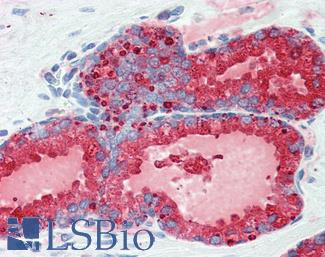

Progesterone Receptor / PGR

Anti-PGR / Progesterone Receptor antibody IHC of human uterus. Immunohistochemistry of formalin-fixed, paraffin-embedded tissue after heat-induced antigen retrieval. Antibody LS-B2983 concentration 20 ug/ml.